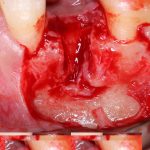

Кстати, обрати внимание на ширину альвеолярного гребня (левая картинка). Она чуть меньше 3 мм. Это объясняет, почему я засомневался в возможности установки имплантатов одновременно с остеопластикой. Понятно и без КЛКТ.

Наперво, мне нужно удалить разрушенный зуб и получить костный аутотрансплантат.